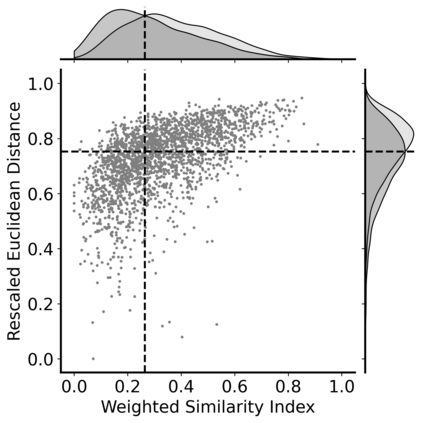

Super-resolution, in-painting, whole-image generation, unpaired style-transfer, and network-constrained image reconstruction each include an aspect of machine-learned image synthesis where the actual ground truth is not known at time of use. It is generally difficult to quantitatively and authoritatively evaluate the quality of synthetic images; however, in mission-critical biomedical scenarios robust evaluation is paramount. In this work, all practical image-to-image comparisons really are relative qualifications, not absolute difference quantifications; and, therefore, meaningful evaluation of generated image quality can be accomplished using the Tversky Index, which is a well-established measure for assessing perceptual similarity. This evaluation procedure is developed and then demonstrated using multiple image data sets, both real and simulated. The main result is that when the subjectivity and intrinsic deficiencies of any feature-encoding choice are put upfront, Tversky's method leads to intuitive results, whereas traditional methods based on summarizing distances in deep feature spaces do not.